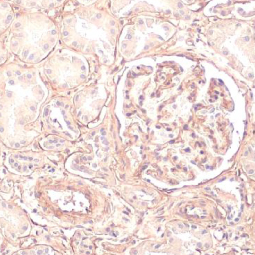

COL4A1 antibody [HL1351] (GTX636771)

Orthogonal Validation